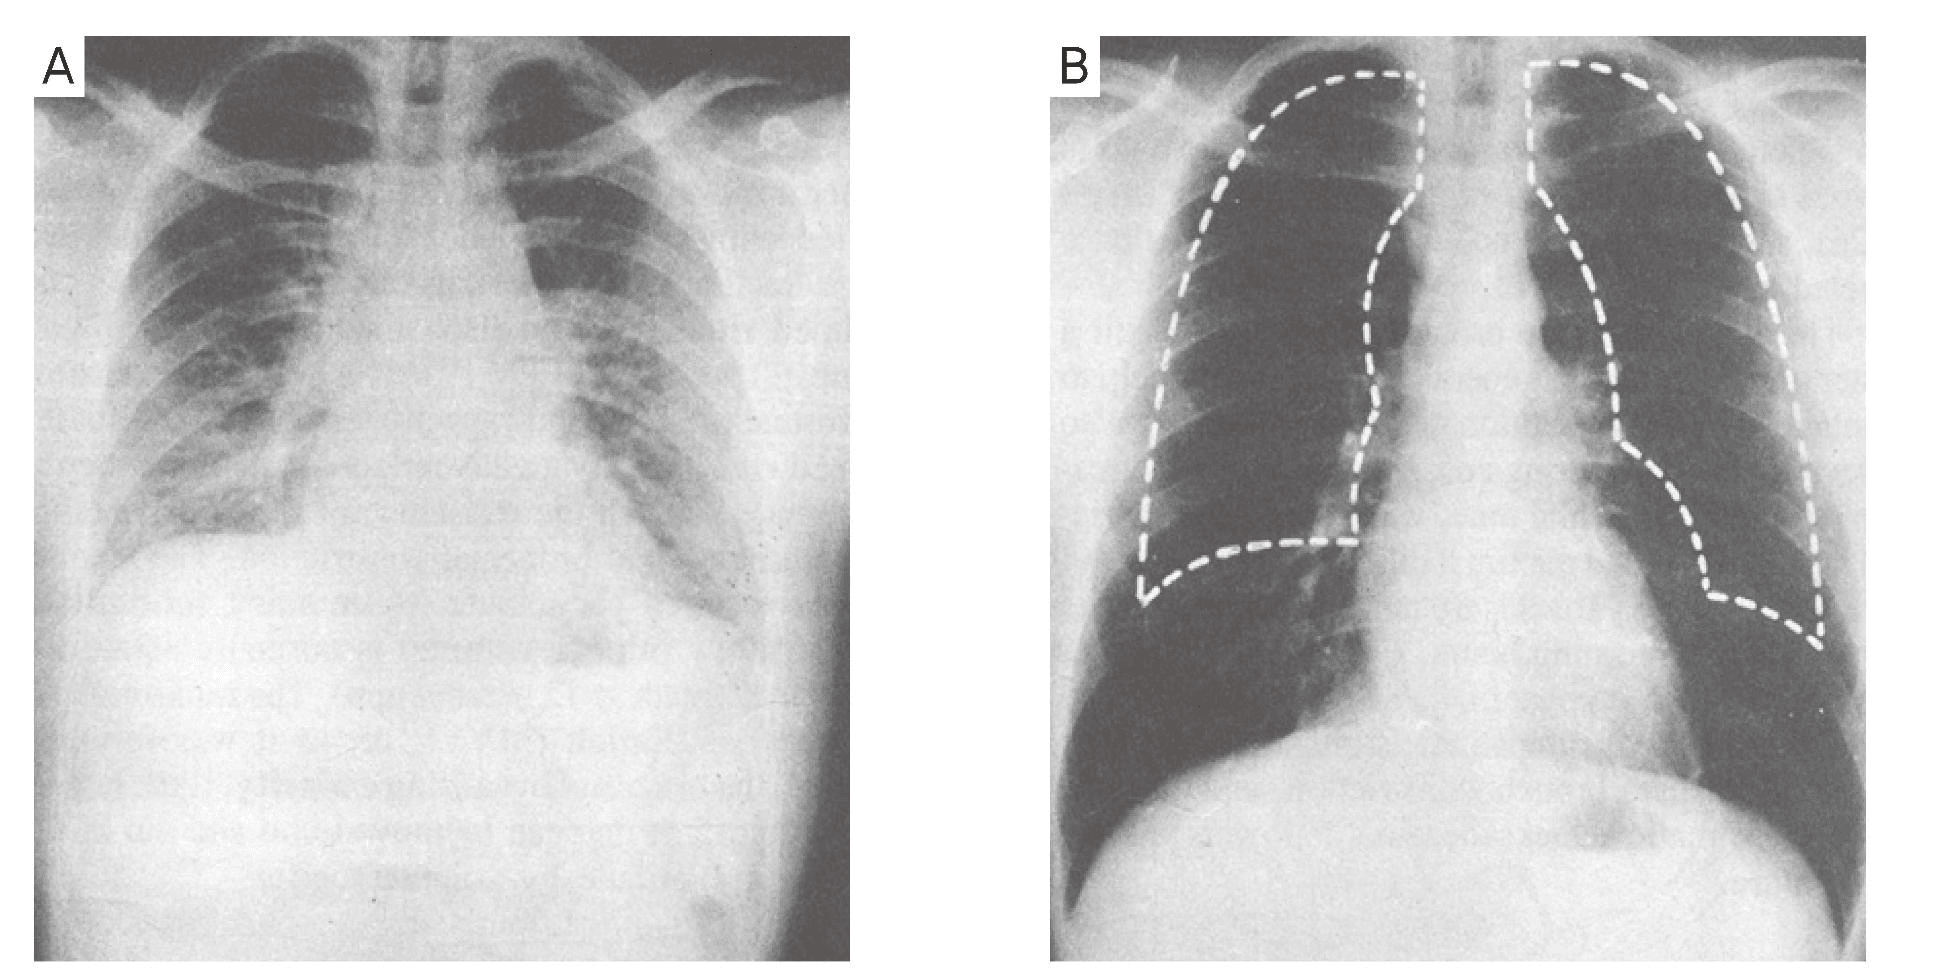

만약 표면활성제 가 적절하게 분비되지 않으면 폐포는 허탈된다.

급성 호흡곤란 증후군을 포함한 많은 호흡계 질환은 표면활성제 부족 때문에 발생할 수 있다.